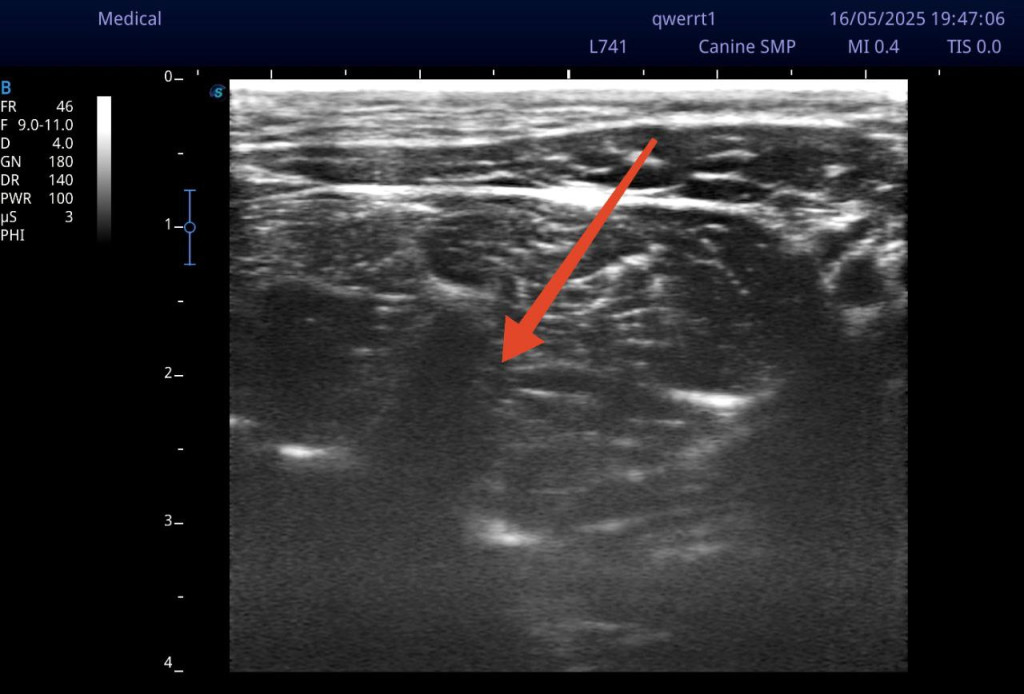

Датчик УЗИ располагается на латеральной поверхности шеи, поперек плоскости оси шейных позвонков (рис. 5). Сканирование начинается от первого шейного позвонка, смещаясь каудально. Шейные позвонки с первого по третий имеют характерные анатомические отличия, облегчающие идентификацию необходимых структур. Стоит уточнить, что кости на УЗИ не просвечиваются, так как ультразвук отражается от поверхности кортикального слоя, формируя изображение. Первый шейный позвонок (атлант) при УЗ-сканировании латеральной поверхности шеи имеет характерные анатомические особенности. Крылья атланта имеют значительную длину и ширину, что позволяет пропальпировать их перед сканированием и установить датчик в эту область, сразу обнаружив на экране силуэт, напоминающий большую тонкую волну, вершина которой направлена перпендикулярно плоскости сканирования. Второй шейный позвонок (эпистрофей/аксис) характеризуется самым маленьким, едва различимым при сканировании поперечным отростком, но отличается довольно массивными суставными отростками. К тому же поперечный отросток эпистрофея может частично перекрывать визуализацию вентрального бугорка поперечного отростка третьего шейного позвонка. Третий и последующие шейные позвонки имеют схожую типичную анатомическую структуру. Основной мишенью визуализации при блокаде будут именно поперечные отростки шейных позвонков. В своем составе поперечный отросток в его краниальной части имеет маленький вентральный бугорок, который при сканировании будет определяться как небольшой выступ, направленный к плоскости сканирования под углом примерно 45°. В каудальной части также имеется более длинный дорсальный бугорок, который чаще обращен к плоскости сканирования перпендикулярно. Таким образом, чередуя вентральные и дорсальные бугорки, можно безошибочно определить необходимый нам анатомический ориентир.

При визуализации дорсального бугорка третьего шейного позвонка можно увидеть фасцию, прилегающую к поперечным отросткам, в виде гиперэхогенной линии, отходящую перпендикулярно (при этом параллельно сканированию). Введение спинальной иглы осуществляется с вентролатеральной стороны в фасциальное пространство между длинной мышцей шеи и длинной мышцей головы до соприкосновения с поперечным отростком (рис. 6, 7).